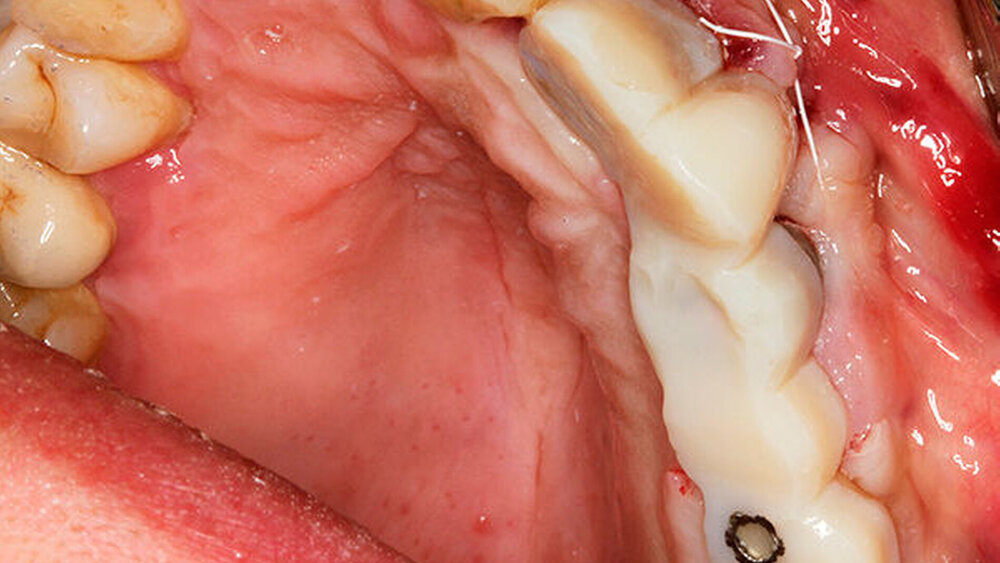

Wir haben extrahiert, dann die Implantate inseriert, direkt nach der Implantation die Scanbodys aufgesetzt, den optischen Abdruck genommen und das Langzeitprovisorium aus PMMA verschraubt. Dass die Innenverbindung immer die gleiche ist, hilft dabei sehr. Eine Prothetik passt tatsächlich auf alle Implantate.

Ich auch, entsprechend konservativ sieht unser Konzept aus, nach dem ich auch meine Frau behandeln würde. Ich ziehe den nicht erhaltungswürdigen Zahn, lege Kollagen ein, kein KEM, um das Blutkoagulum zu stützen. Nach sechs Wochen setze ich entsprechend den prothetischen Rahmenbedingungen im Frontzahnbereich das Implantat und nach zwölf Wochen im Seitenzahnbereich. Die bukkale Lamelle stabilisiere ich mit einem resorptionsstabilen KEM. Dann erfolgt die Abdeckung mit einer Membran (GBR). Für dieses Vorgehen gibt es sehr schöne Zehnjahresergebnisse von Chappuis et al. aus der Berner Arbeitsgruppe, die letztes Jahr veröffentlicht wurden. Für diese Indikation würde ich auch ein BLX verwenden.